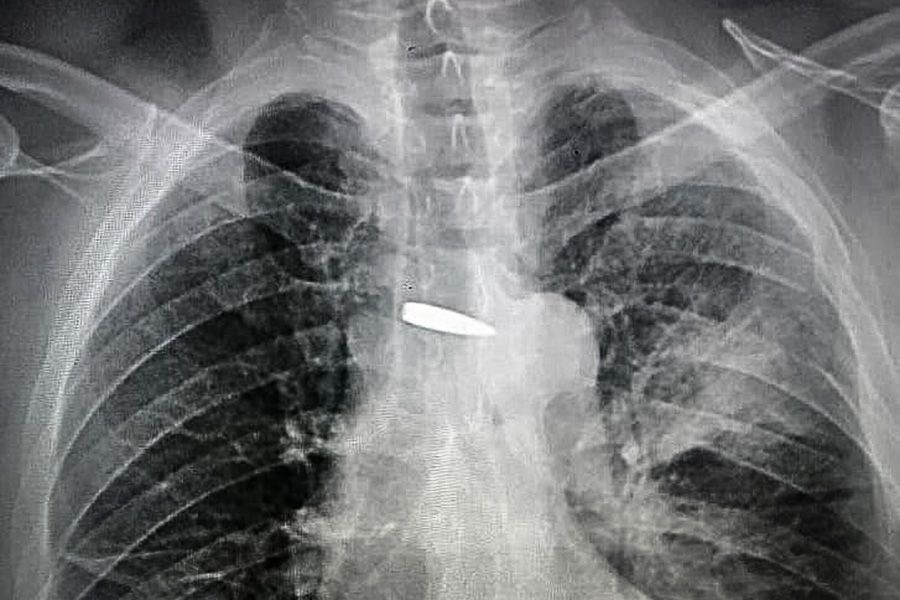

Рентгенівський знімок кулі біля його серця облетів весь світ. У середині лютого окупанти поранили Віталія в груди. П’ять днів він боровся в реанімації зі смертю.

Кулю хірурги Хмельницької міської лікарні оперативно вилучили. А в день народження подарували врятованому.

Згодом Віталій дізнається, що куля пройшла крізь ліве плече, ліву легеню буквально в міліметрах від серця та роздробила поперечний відросток п‘ятого грудного хребця.

Хмельницьким лікарям вдалося визначити до міліметра її місце розташування та, завдячуючи професійності та новітньому обладнанню, швидко витягнути.